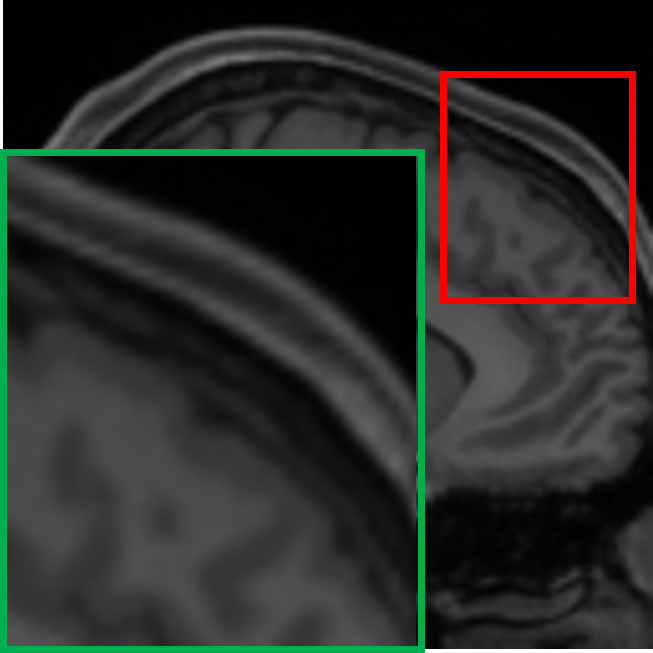

IV-C Visualization of the expert specialization

To further elucidate the functional specialization of each expert within the proposed MoE framework, we visualize the difference maps between each expert’s output and the ground truth 7T MRI. These maps are computed by taking the pixel-wise absolute difference between the expert output and the ground truth 7T MRI, highlighting the residual discrepancies and reconstruction focus of each expert. In the visualizations, lighter areas reflect lower reconstruction errors, suggesting better alignment with the ground truth. As shown in Fig. IV, each column represents the output of a particular expert, visualized through its corresponding absolute difference map with respect to the 7T reference. The final output is computed via a weighted combination of expert outputs. The visualized difference maps underscore the distinct specialization of each expert. Specifically, Expert 1 exhibits minimal residuals in homogeneous white matter regions, preserving large-scale anatomical continuity. Its low-frequency focus is evident in the smooth residual patterns and coherent structural boundaries. Expert 2 demonstrates heightened sensitivity to cortical regions and sulcal boundaries, with pronounced residual suppression around edges and high-frequency details. Expert 3 shows enhanced reconstruction accuracy at tissue interfaces and transitional zones. The residuals are particularly reduced in regions of sharp contrast changes. These observations confirm that each expert effectively targets specific anatomical and textural characteristics, guided by their unique architectural and loss function design. The gating mechanism further facilitates optimal integration by adaptively weighting expert contributions according to the local image context, thus ensuring a globally coherent and anatomically faithful 7T-like reconstruction.

TABLE IV: Visualization of the expert specialization

E1subscript𝐸1E_{1}italic_E start_POSTSUBSCRIPT 1 end_POSTSUBSCRIPT E2subscript𝐸2E_{2}italic_E start_POSTSUBSCRIPT 2 end_POSTSUBSCRIPT E3subscript𝐸3E_{3}italic_E start_POSTSUBSCRIPT 3 end_POSTSUBSCRIPT Final

[Uncaptioned image] [Uncaptioned image] [Uncaptioned image] [Uncaptioned image]

𝒢1=0.21subscript𝒢10.21\mathcal{G}_{1}=0.21caligraphic_G start_POSTSUBSCRIPT 1 end_POSTSUBSCRIPT = 0.21 𝒢2=0.48subscript𝒢20.48\mathcal{G}_{2}=0.48caligraphic_G start_POSTSUBSCRIPT 2 end_POSTSUBSCRIPT = 0.48 𝒢3=0.31subscript𝒢30.31\mathcal{G}_{3}=0.31caligraphic_G start_POSTSUBSCRIPT 3 end_POSTSUBSCRIPT = 0.31 Weighted

• *

The expert-specific weights (𝒢1subscript𝒢1\mathcal{G}_{1}caligraphic_G start_POSTSUBSCRIPT 1 end_POSTSUBSCRIPT, 𝒢2subscript𝒢2\mathcal{G}_{2}caligraphic_G start_POSTSUBSCRIPT 2 end_POSTSUBSCRIPT, 𝒢3subscript𝒢3\mathcal{G}_{3}caligraphic_G start_POSTSUBSCRIPT 3 end_POSTSUBSCRIPT) for this particular slice are dynamically computed by the gating network 𝒢𝒢\mathcal{G}caligraphic_G.